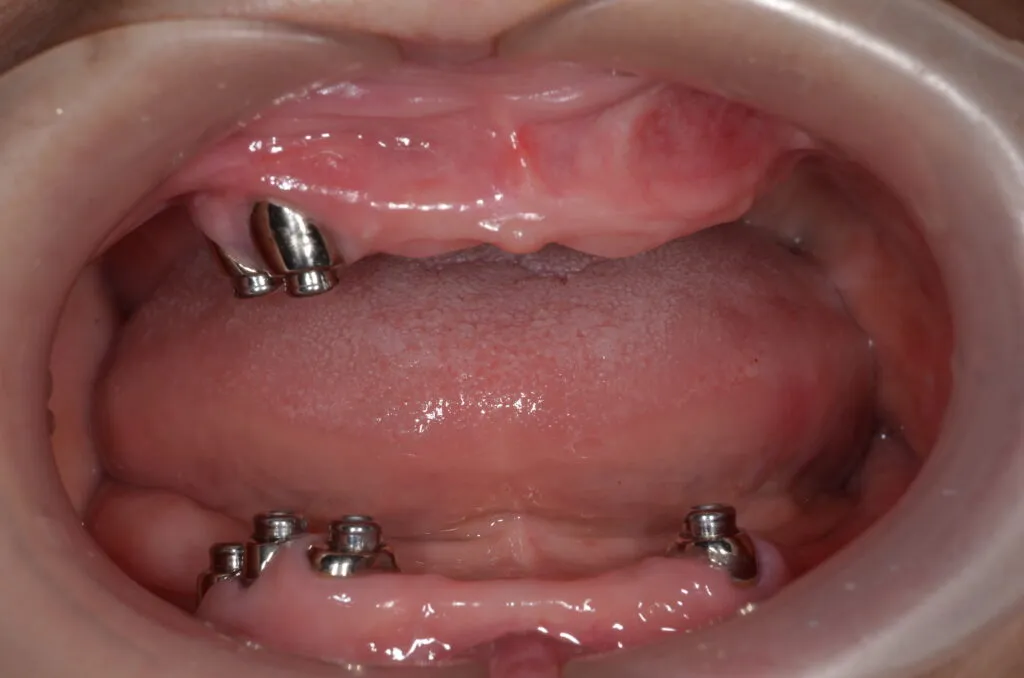

アタッチメント義歯

義歯で一番難しいのは総入れ歯で、特に下が総入れ歯になると多くは骨が無くなっているため、入れ歯が安定せずに、食べられないという悩みも多く聞きます。そのため、義歯作製に多くの特殊な知識・技術が必要となります。

当院では、下あごにピッタリと吸着し、リンゴや堅い煎餅でもしっかりと噛める快適な義歯をご提供いたします。